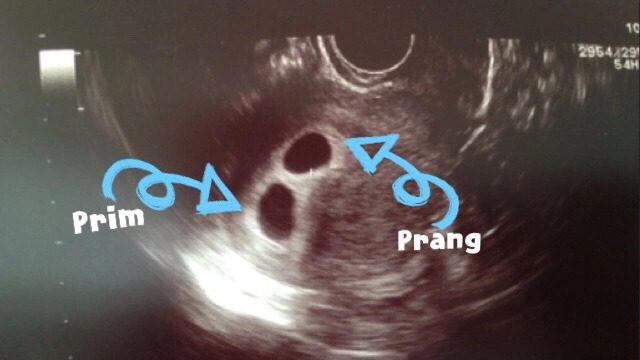

- ครั้งนี้จะขอใส่ 3 เลยจะได้มีโอกาสเพิ่มขึ้น ปรากฏสามีไม่อนุญาต หมอก็กลัวติด 3 สรุปใส่ไป 2 เหมือนเคย คราวนี้นอนนิ่งๆ 5 วันและสอดยาลึกๆสุดปลายนิ้ว (ก่อนหน้านี้กลัวยาไปชนลูกแต่ถามหมอละ หมอบอกสอดยังไงก็ไม่ถึงหรอก) ปรากฏว่าเวิร์ค แอบตรวจได้ 2 ขีดตั้งแต่วันที่ 7 หลังย้ายตัวอ่อน พอวันที่ 10 นัดเจาะเลือดได้ hCG 200 กว่าๆ กริ๊ดดดดด ท้องแล้ว ระหว่างนั้นก็เหมาที่ตรวจมาตรวจเป็นสิบๆอันแบบว่ารอมานานไม่เคยเห็นสองขีด ฮาๆๆๆ วันที่ 14 อาการแพ้ท้องเริ่มมา ทำไมมันไวจังวุ้ย สามีบอกกระแดะ 555 สรุปว่าได้แฝดฮอร์โมนเลยเยอะ ทำให้แพ้ท้องไวกว่าชาวบ้าน ดีใจมากๆ ตอนที่รู้ว่าท้องแล้ว รวมเวลาเกือบ 2 ปีกว่าจะได้เบบี๋ // ไม่คิดเหมือนกันว่าจะมีวันนี้ วันที่มีลูกได้ มองหน้าลูกยังนึกนี่เรามีลูกจริงๆเหรอเนี๊ยนี่แค่เริ่มต้นของลูกแฝดนะคะ อุปสรรคการอุ้มท้องแฝดตอนต่อไปค่ะ